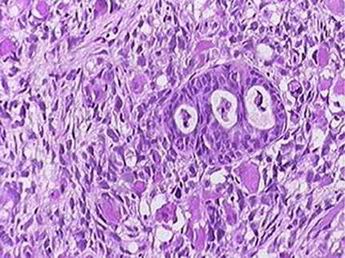

Patologie dlaždicového epitelu invazivní karcinom

CIN III

Mikroinvazivní karcinom < 3mm